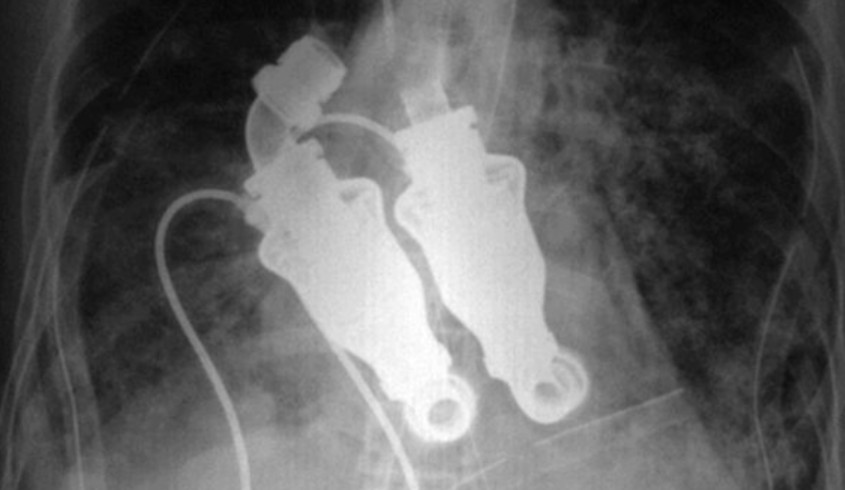

С согласия супруги Льюиса, Линды, хирурги установили ему искусственное сердце, созданное из самодельных деталей. После операции пациент прожил пять недель, хотя до нее прогнозировалось, что он не доживет и до 12 часов.

Перед этим экспериментом ученые провели более 50 успешных испытаний на телятах. В ходе экспериментов у животных удаляли сердца, но благодаря установленному устройству они уже через сутки вели обычную жизнь – ели, спали, передвигались. Их кровообращение поддерживалось не сердечным пульсом, а непрерывным потоком, обеспечиваемым специальными лопастями устройства.